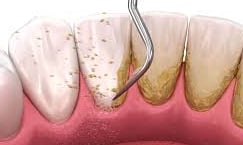

Deep Cleaning, also called Scaling and Root Planing (SRP), is a non-surgical treatment for gum disease. During this procedure, the hygienist cleans deep under the gums and smooths the roots of your teeth. This reduces inflammation, stops infection from getting worse, and helps gums heal and reattach to the teeth.

Deep cleaning, also known as scaling and root planing, is used to treat gum disease by removing plaque and bacteria from below the gum line and smoothing the tooth roots to help gums heal properly. Depending on the severity of the condition, the treatment may be completed in sections (such as half-mouth or quadrant visits) to ensure comfort and thorough care. After deep cleaning, ongoing periodontal maintenance visits every 3–4 months are essential to keep gum disease under control, as regular cleanings are not sufficient once periodontal issues are present.

Scaling — removing buildup from below the gumline

Root planing — smoothing the roots to help gums heal